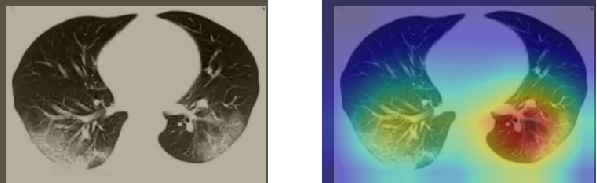

A wide variety of typical and atypical CT abnormalities have been reported for COVID-19 patients in various studies [58, 59]. So, we tested our models on external CT images extracted from these two publications as they feature typical findings of COVID-19 pneumonia marked by specialists. In order to make sure that not any of the extracted images are unintentionally included in our datasets, specifically the COVID19-CT dataset, we use the model trained on the SARS-CoV-2 dataset. First, the InceptionV3 model is employed to classify the extracted CT images. The model is able to correctly classify the given CT images as COVID-19. Second, in order to interpret the model’s generalization capabilities, we apply the Grad-CAM technique to visualize the regions of abnormalities that are considered. By assessing the different CT images in Figure 15, we can see that the model accurately localizes the disease-related regions. Even more interesting is the fact that the model ignores any specific marks in the images like letters and only localizes the COVID-19 related regions. These visual explanations show the success of our models to learn relevant, generic visual features related to COVID-19 and are capable to correctly classify CT images outside the datasets on which they are trained.

Figure 16 shows various CT scans where only one lung is visible. The CT scans are also extracted from the paper [58] and show different CT manifestations of COVID-19 pneumonia marked by red squares. The InceptionV3 model is capable to classify them correctly as COVID-19, although it is trained on CT scans where the entire lung is visible. Intriguingly, when applying Grad-CAM we can see that all regions of abnormalities are accurately localized. This also proves the potential of our model to detect COVID-19 abnormalities in CT images outside the dataset used for training.